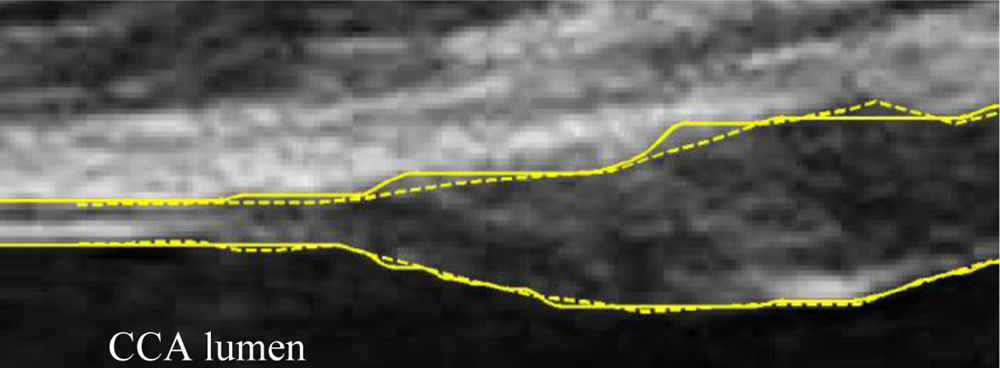

A typical B-mode image is shown in Figure 1. There are plaques on both near and far walls. On the contrary, a typical CCA image without plaque having thin and thick IMT is shown in Figures 2 and 3, respectively. Outlining the boundaries of intima and adventitia is not easy, especially on the near wall. Some features have been studied in previous studies [7,11], in which the most frequently used feature is the gradient of gray-values. From our previous studies [7,14,17], it is found that MacLeod operator combined with some specific enhancement filters are very suitable for feature extraction in intima and adventitia detections.

Figure 14 depicts our manual drawing GUI. The solid lines denote the boundary of the automated analysis. The dashed lines denote where the expert should give their judgment on the lumen-intima interface. Manual drawing involves a tremendous amount of human work. Although we are not able to provide many manual drawings for comparison, however, the automated results were controlled visually by experts and all results are similar to those shown in Tables 1 and 2. The system is built on the Matlab platform. Some kernel functions are written in C language in order to reduce the computation time.